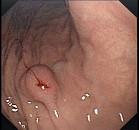

问题 男,23岁,食用海鲜后,出现腹痛、腹胀2天,呕吐,查体,无发热,下肢可见皮疹,B超肝胆正常,胃镜检查如图。最可能的诊断是 ( )

选项 A、阑尾炎 B、消化道出血 C、急性胰腺炎 D、过敏性紫癜 E、急性胆囊炎

答案 D